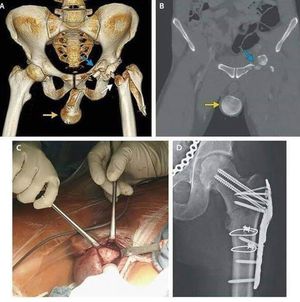

Head of femur in the scrotum!

Motorcycle accident lead to move the head of femur after fracture into the scrotum.